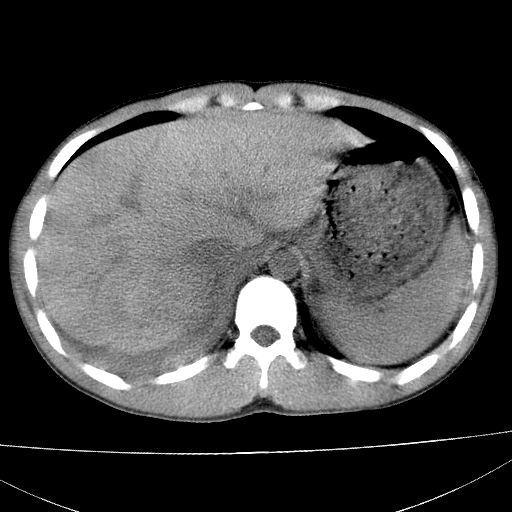

标题: CT15860:男,21岁,腹部外伤2小时伴胸疼。 [打印本页]

标题: CT15860:男,21岁,腹部外伤2小时伴胸疼。

b超示:肝破裂。

肝脏及肾脏明显有损伤性改变并激发腹腔内积液(血),以肝脏撕裂及肾周积血显著。

1)肝破裂伴腹腔积液(血)。2)右肾破裂伴右肾包膜下及肾周血肿。3)腹部空腔脏器穿孔可能。4)右侧少量胸腔积液(血)。